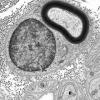

PERIPHERAL NEUROPATHY

2 NORMAL AXON